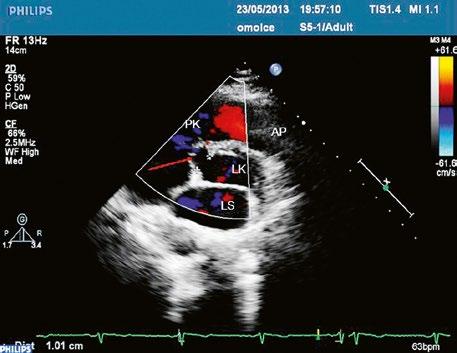

Poslechový nález systolického šelestu nad plicnicí s fixním rozštěpem 2. ozvy je nenápadný. Echokardiograficky je patrná dilatovaná a objemově přetížená pravá komora s paradoxním pohybem septa (Obr. 45.9), zkratový tok může být vidět i transtorakálně (TTE) (Obr. 45.10, Video 45.3, Video 45.7), ale suverénní diagnostickou metodou je jícnová echokardiografie (TEE), případně s 3DE zobrazením (Obr. 45.1, Obr. 45.2,

Obr. 45.10 TTE, čtyřdutinová apikální projekce s levo pravým zkratem na úrovni síní (šipka) při defektu septa síní typu secundum PK – pravá komora, LK – levá komora, LS – levá síň, PS – pravá síň